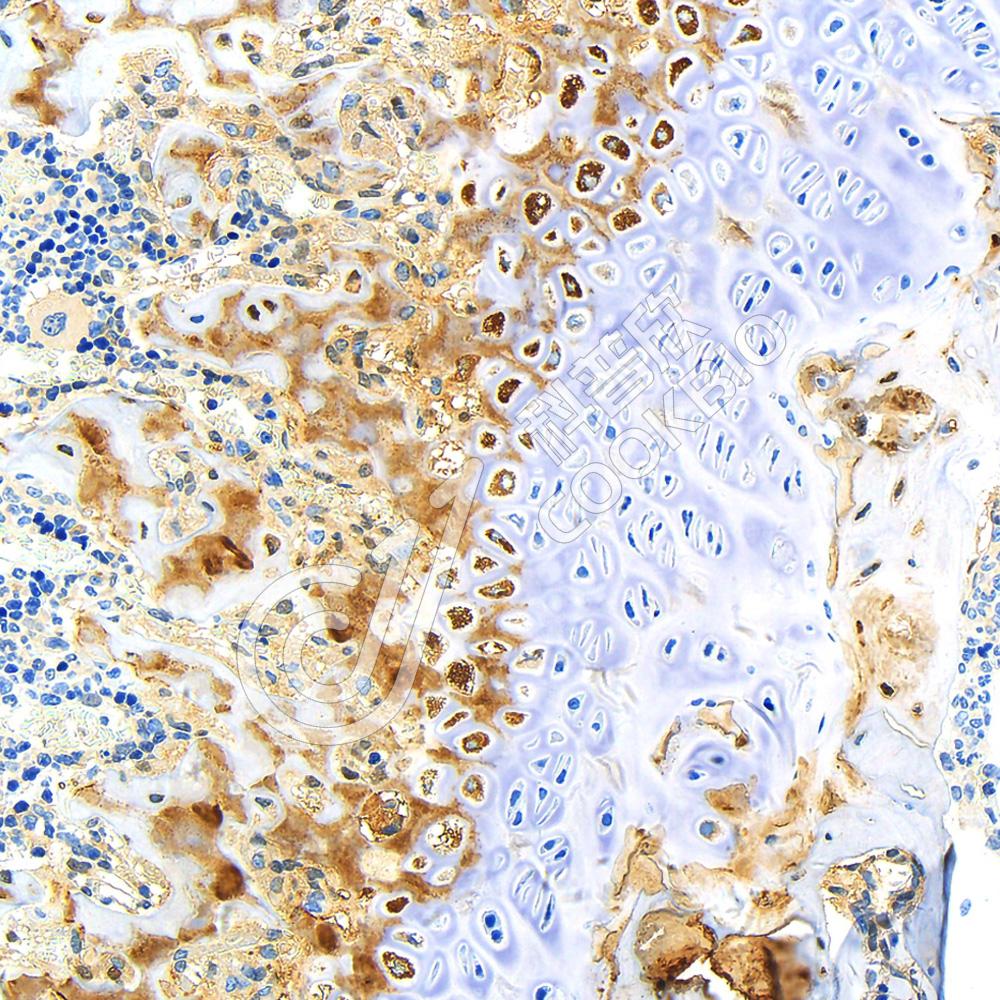

IHC检测p70 S6 Kinase蛋白(货号 K1333543).

样品: 人肝癌, 4%多聚甲醛 (货号KSG1101) 固定12-24小时.

抗原修复: 柠檬酸抗原修复液(干粉, pH 6.0) (KSG1201), 98℃, 20分钟.

—抗: 1: 1300稀释, 4℃ 孵育过夜.

二抗: S-vision免疫组化多聚二抗(山羊抗兔),即用型 (货号KB3906), 室温孵育20分钟.